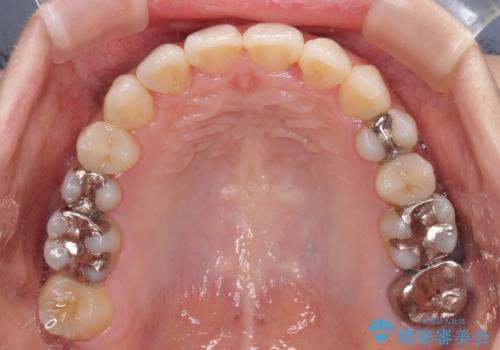

上下の骨幅を改善したことで、スムーズに歯列矯正を行うことができました。

矯正治療中に近医で銀歯を外す治療を開始したため、治療後に奥歯の咬み合わせが不十分ですが(こちらは近医での治療により改善するとのこと)、歯列と咬み合わせが改善され、患者様には大変満足していただきました。